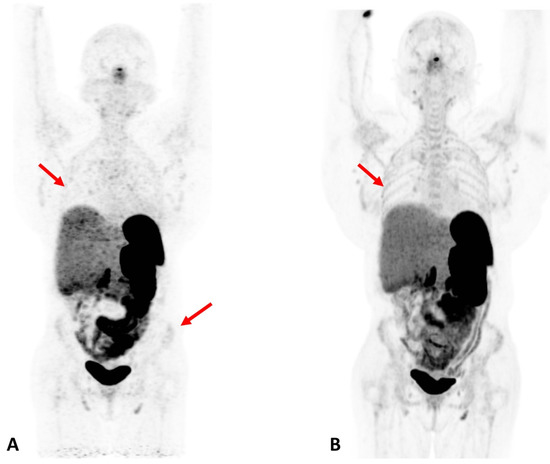

Figure 4.

Patient with Cushing Syndrome post bilateral adrenalectomy. A dose of 167 MBq of 68Ga DOTATATE was injected, and a 20-min scan was performed after 60 min of uptake. (A) Baseline scan obtained on a conventional PET/CT scanner; (B) 6-month follow-up scan obtained on a total-body scanner. In the total-body PET/CT image, background noise is lower and the signal higher, allowing for clearer visualization of the liver. In addition, the increased signal level on the total-body scanner results in new or better visualization of bone details (arrows). Reprinted with permission from Ref. [23]. Copyright 2020 Elsevier.